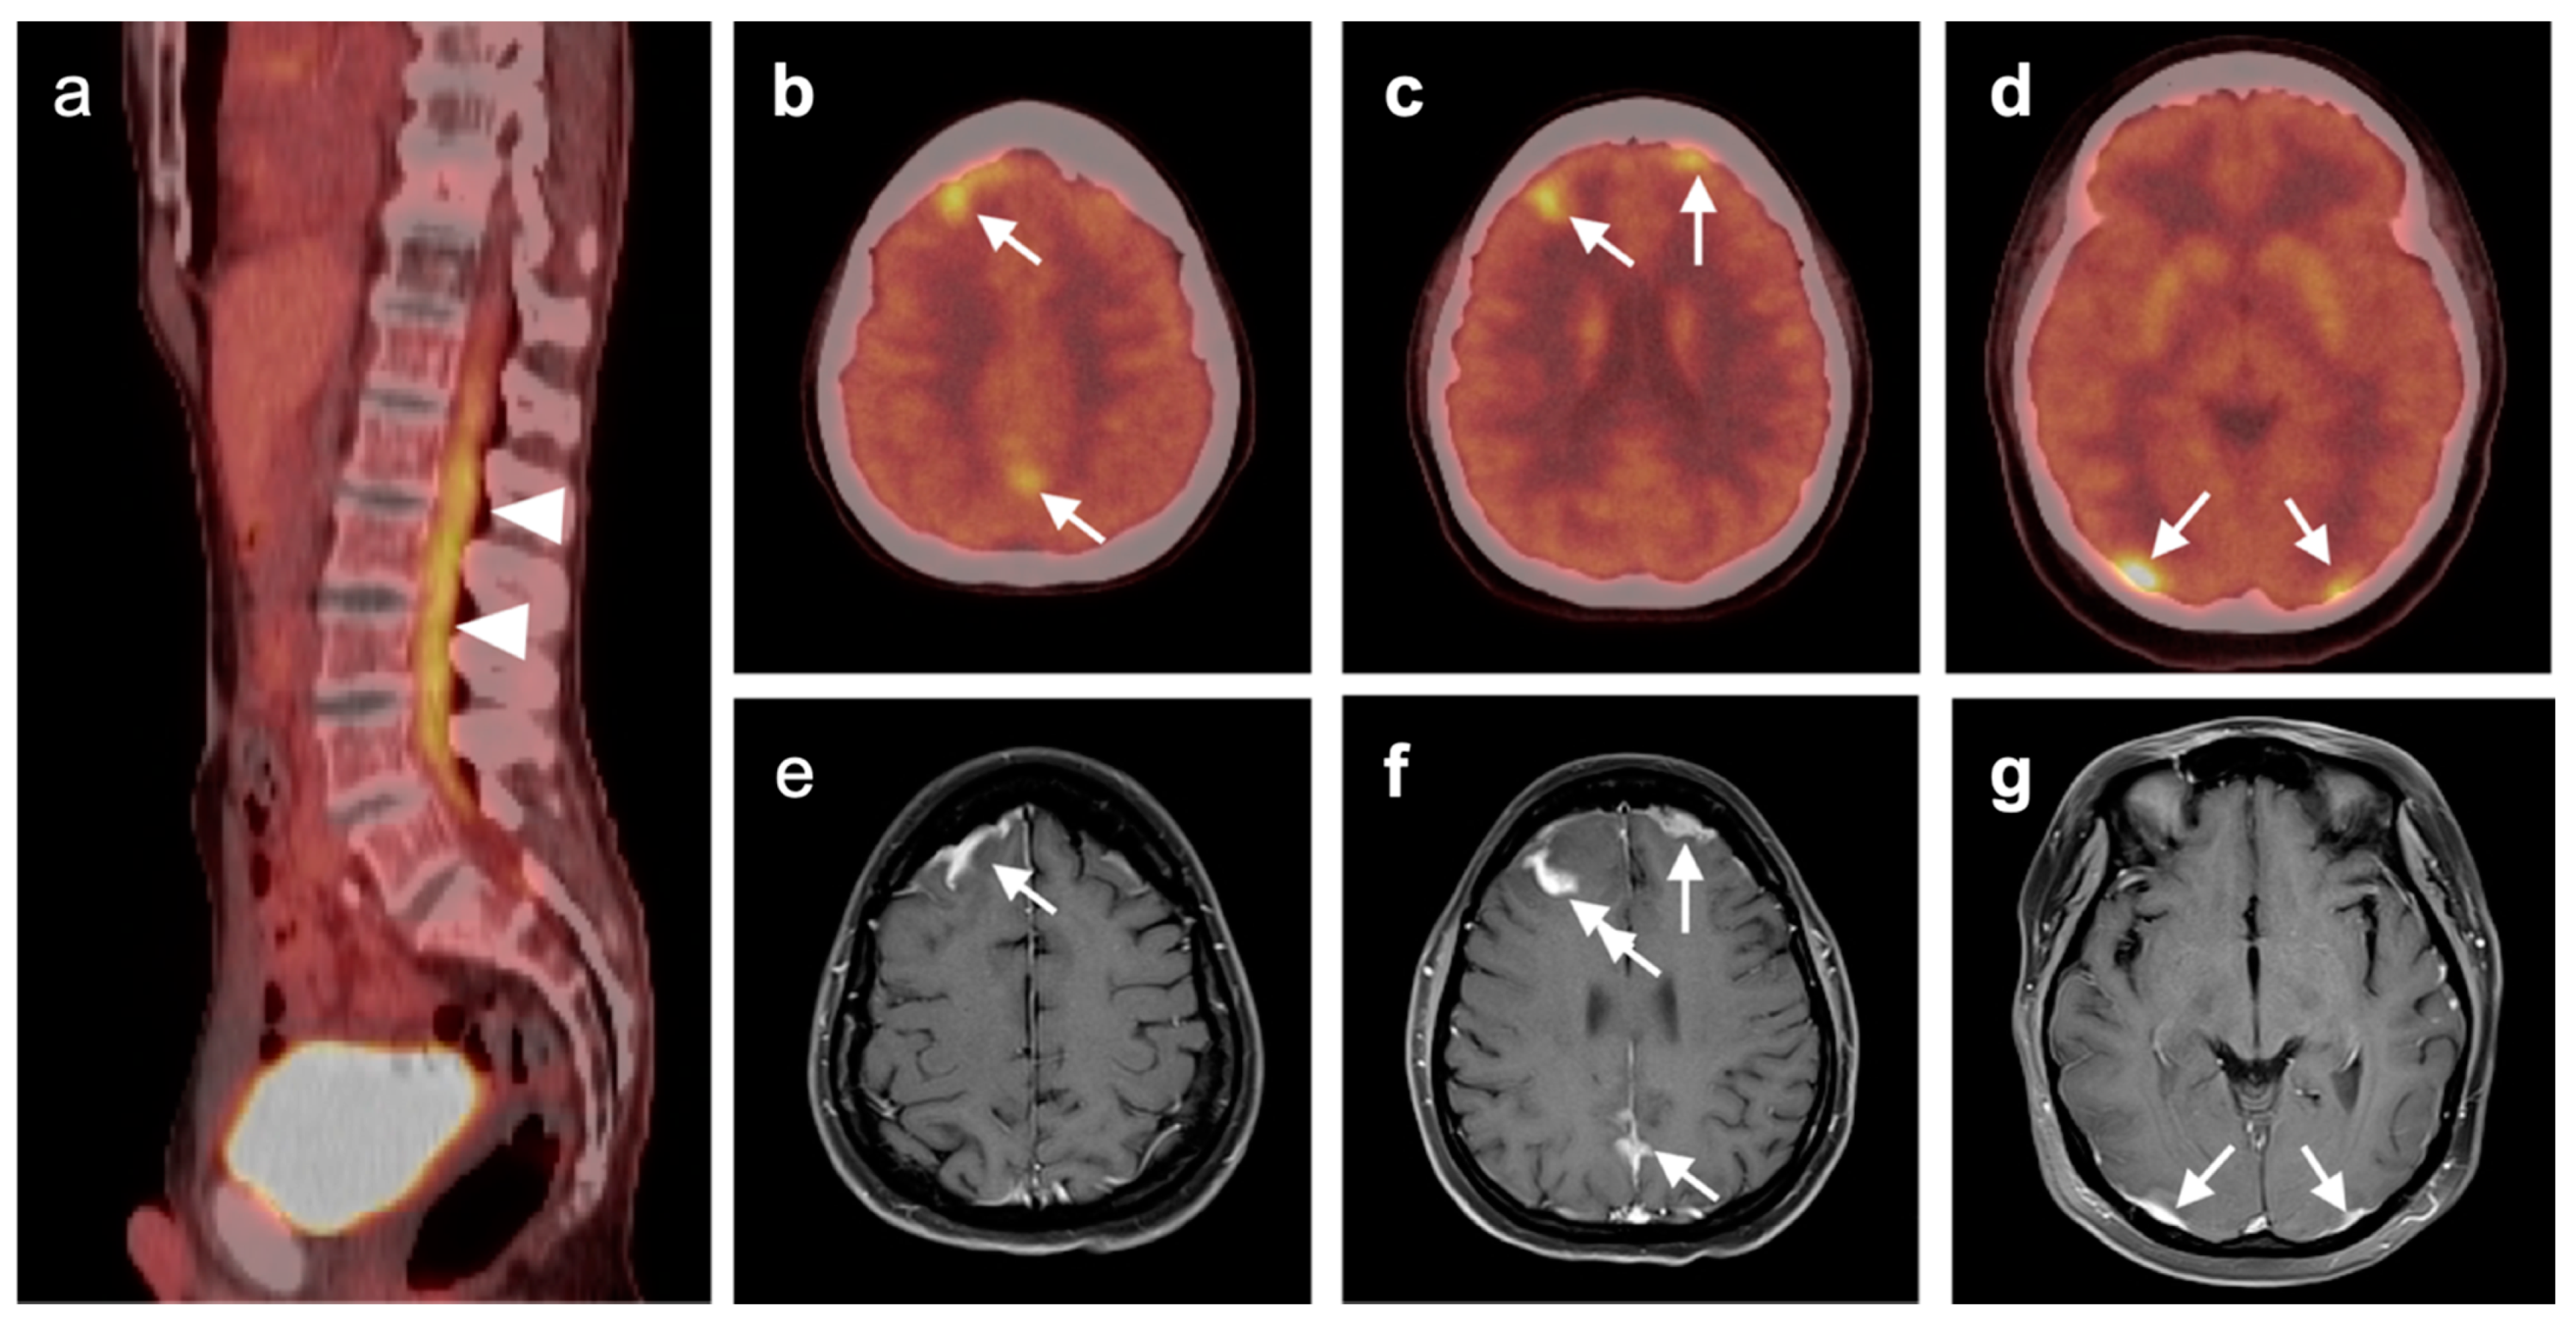

3.5. Brain Metastases

3.6. Response to Therapy

3.7. Meningioma